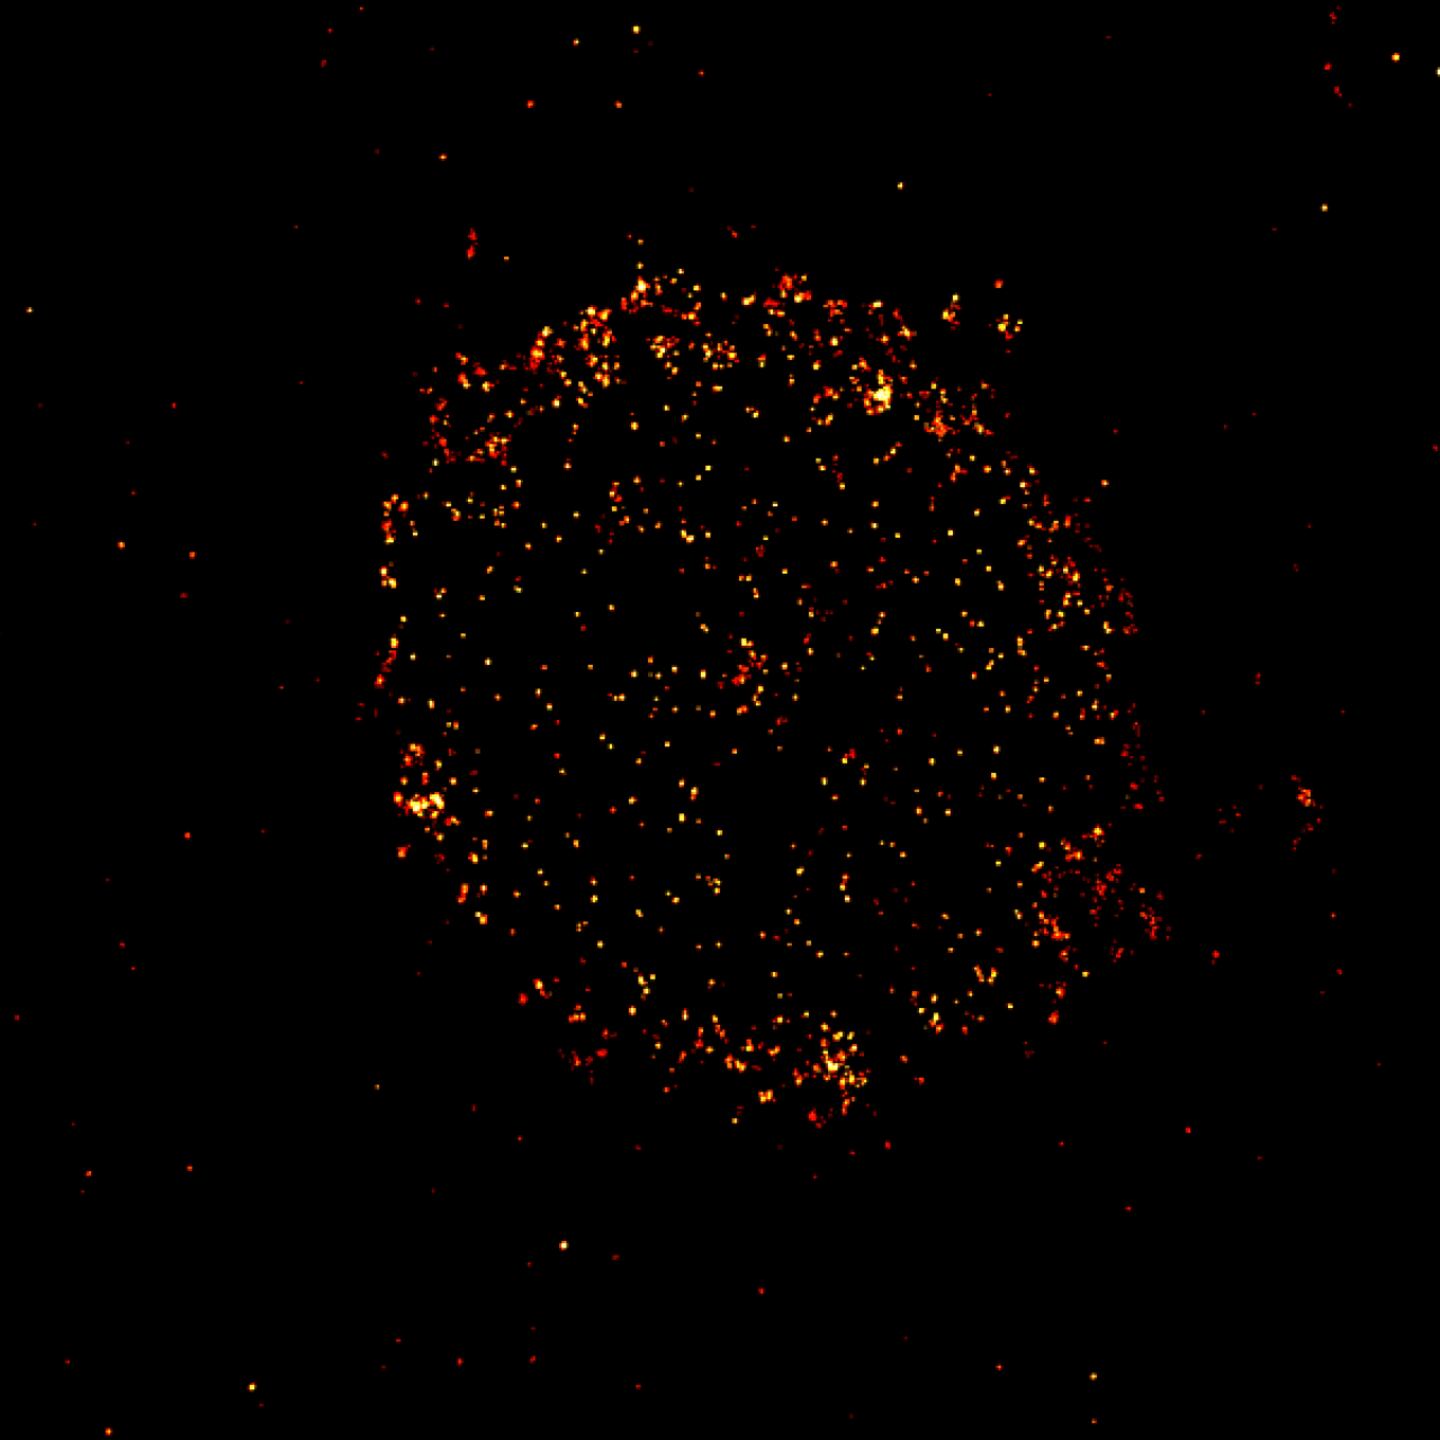

Scientists are also examining cells affected by disease. For example, biophysicist Markus Sauer of the University of Würzburg in Germany is studying certain receptor proteins on the surfaces of cancer cells that are used as targets in cancer-killing therapies. For blood cancers, for instance, scientists have genetically engineered immune cells to find and kill cancer cells that have specific surface proteins.

But the techniques commonly used to analyze the proteins in patients' cancer cells and match patients with effective therapies don't give a full picture, Sauer says. That was illustrated back in 2015, when physicians discovered they could successfully treat patients with the blood cancer multiple myeloma with therapies that target a receptor called CD19 — even though CD19 hadn't been spotted on multiple myeloma cancer cells with standard methods.

Sauer and colleagues found in 2019 that the CD19 proteins were clearly visible with super-resolution microscopy. They learned that to do their killing job, the immune therapies require as few as 10 CD19 proteins among hundreds or thousands of other proteins on a cancer cell surface.

Markus Sauer

These microscopy techniques can be used to better match patients to effective therapies, Sauer says. His more recent research has identified a new receptor protein for therapies to target, and helped elucidate the exact process of tumor killing — knowledge that could help improve the potency of immune therapies. "You have to visualize those processes at molecular level," he says.